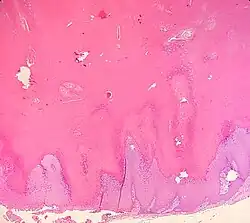

| Upper back of a middle-aged man. Present for years. | |

Verrucous cysts are a cutaneous condition that resemble epidermoid cysts except that the lining demonstrates papillomatosis.[1]: 681